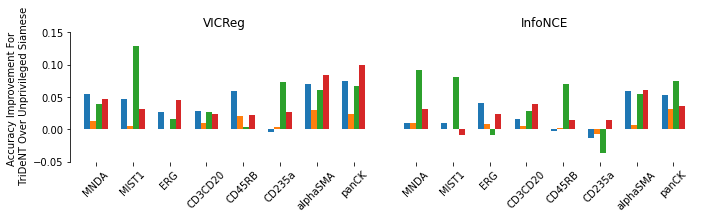

We first demonstrate that TriDeNT ♆ is highly effective for improving the quality of representations in the primary encoder by distilling privileged information from immunofluorescence (IF) images to H&E stained images (Figure 2 and Table S6). Models are trained on the SegPath dataset [22], which consists of eight subsets of H&E images paired with an image derived from the IF stain of a consecutive slice for one of eight antibodies. Evaluation is performed on four standard computational pathology tasks (see Section S2 for full details). We find that the model significantly increases performance by up to 101% compared to a privileged baseline model. TriDeNT ♆ retains not only the useful features shared between inputs, but also the features which are only present in the primary data, leading to better performance on all evaluated tasks. Even in cases where the privileged data does not appear to significantly improve performance, such as staining with CD235a, TriDeNT ♆ still achieves comparable performance, as it obtains a strong supervisory signal from the additional H&E branch. This is in contrast with the privileged Siamese setting, where it is clear that the pairing can cause a seismic drop in classification accuracy if the privileged data is not informative for the task being evaluated.

The performance of TriDeNT ♆ is noticeably more polarised for the InfoNCE loss than for the VICReg loss, as its best accuracies are higher but its performance is lower on average, despite its performance in the simple Siamese setting being higher than that of VICReg on these tasks. This could be because VICReg is explicitly designed to handle different inputs on each branch, with each representation being regularised separately, as opposed to InfoNCE which has no such process.

We see that there are significant performance gains of up to 101% (0.4566 to 0.9169, see Table S6) in the NCT tissue type classification task for TriDeNT ♆ against the baseline privileged method. Perhaps unsurprisingly given the diagnostic importance of cytokeratin stains for detecting tumours, the greatest increase – 9.0% – in performance against the unprivileged baseline method was achieved for the pan-CK model, with similar gains for SMA. Compared to the baseline unprivileged method, there was less benefit for pairing CD235a or ERG (-0.5% and +3%), perhaps because red blood cells (stained by CD235a) and the endothelium (stained by ERG) were less present in the NCT slides. Still, compared to the baseline privileged method, performance on CD235a and ERG was significantly improved, by 51% and 56% respectively.

In the PanNuke neoplastic cell detection task, we see that in Siamese models, some stains help improve prediction accuracy while others hinder it. For example, privileged Siamese training is considerably less accurate for MIST1 and ERG stains, which stain plasma and endothelial cells respectively, while it is more accurate for SMA and pan-CK, which stain smooth muscle cells/myofibroblasts and epithelial cells respectively. There is simply more semantic content in the SMA and pan-CK masks due to their lower percentage of black space, which is likely to explain this disparity. For this reason, it is difficult to draw strong conclusions about whether certain stains are more effective as privileged data than others, leaving this as an interesting avenue for future work. We also note that there are some small differences in the distributions and sample sizes of the tissue samples used for different stains, as the unprivileged models have a range of 0.0533 for their accuracies on the tissue type classification task. The differences are even less for the PanNuke neoplastic cell detection task, as these have a range of 0.0321.